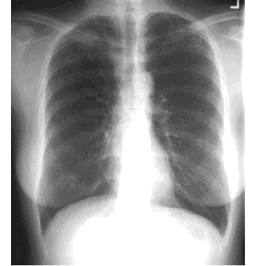

CASE 2

How would you describe the LUNG abnormality in each of these cases?

A